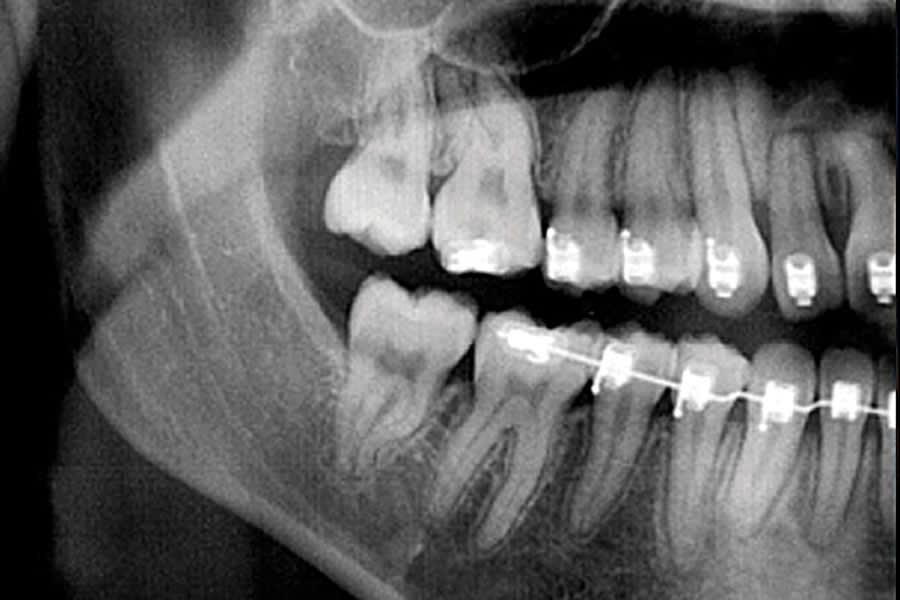

In a radiograph acquired prior to the removal of a patient's orthodontic hardware, a mid-crown radiolucency was noted on the maxillary right first molar (ie, tooth No. 3) (Figure 1). A visual examination of the crown did not indicate the presence of an obvious Class I lesion at the surface (Figure 2); however, the initial access revealed a penetrating caries lesion (Figure 3). After all of the soft carious substance was debrided, the preparation was disinfected by completing two 60-second soaks using a universal desensitizing agent with glutaraldehyde (MicroPrime™ G, Zest Dental Solutions) (Figure 4).3 Next, a round diamond bur was used to remove all of the carious dentin and establish proper retention form (Figure 5). Dentin replacement was achieved with a resin-modified calcium silicate-filled liner (TheraCal LC®, BISCO, Inc) (Figure 6). To replace the enamel, a self-etching bonding agent was applied (Adper™ Prompt™ L-Pop™, 3M) (Figure 7) followed by a bioactive resin-modified glass ionomer (RMGI) restorative material (ACTIVA™ BioACTIVE-RESTORATIVE™, PULPDENT), which was injected to overfill (Figure 8). After a curing light beam was applied for two 20-second exposures (1,200 mW/cm2) (Figure 9), a round diamond bur was used at slow speed to shape the occlusal contour (Figure 10). A final layer of the self-etching bonding agent was then applied to "glaze" the surface and improve the seal of the restoration (Figure 11), after which the occlusion was evaluated (Figure 12). The restoration was found to still be in excellent function with no signs of secondary decay or other complications at both a 2-year postoperative follow-up (Figure 13 and Figure 14) and a 5-year, 2-month postoperative follow-up (Figure 15 and Figure 16).